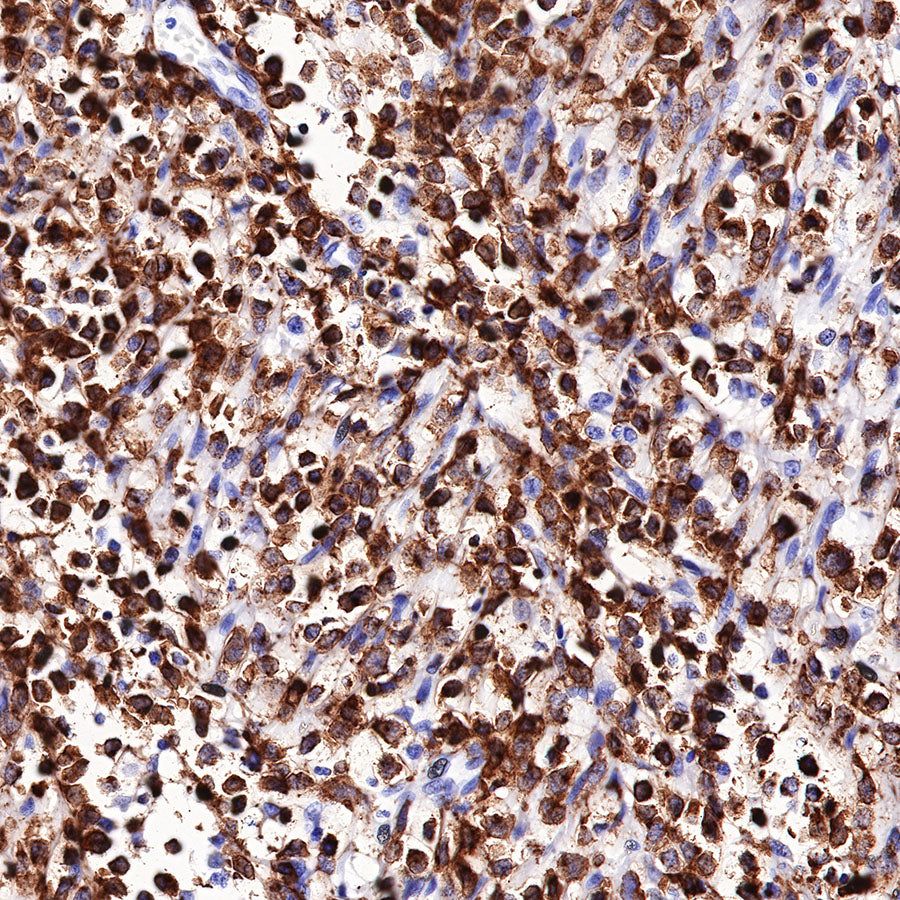

Immunohistochemistry